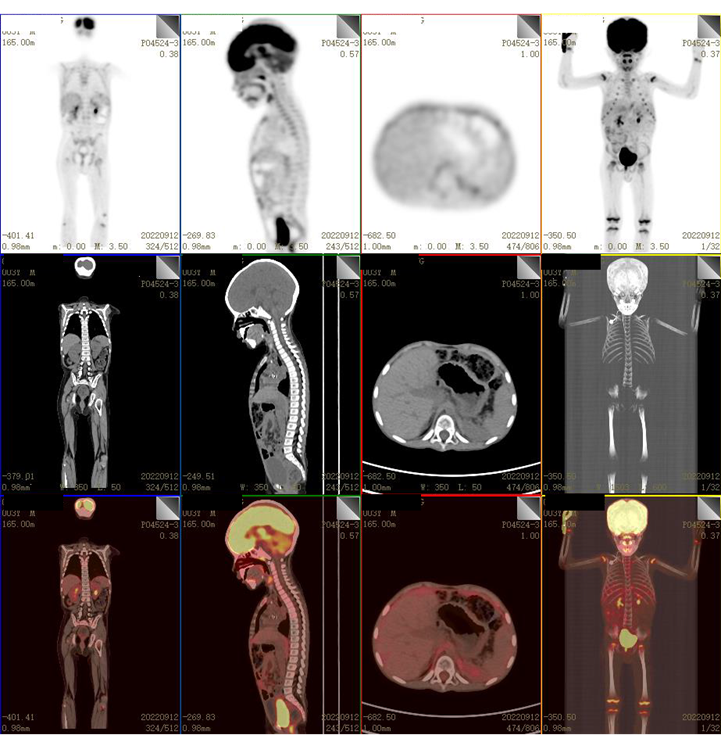

PET/CT(2021.08.14)

中上腹腔见多发不规则巨大囊实性占位(最大层面约14.7cm × 12.2cm × 13.7cm),实性区代谢增高,考虑恶性肿瘤,以NB可能大。左侧膈上、肌脚后间隙、右肾门区及腹膜多发高代谢肿大淋巴结及软组织包块,考虑转移。

2022.09.12(第2周期后)

复查PET/CT:未见明确高代谢灶。